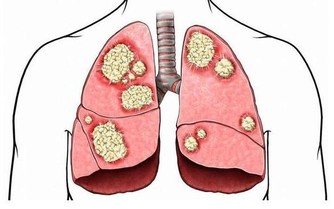

其實,不僅僅是鼻咽癌手術,鼻部疾病尤其是鼻炎,採用手術治療同樣有很大的風險。

多數鼻炎手術的本質是破壞鼻粘膜

我們常見的鼻炎手術手段,無論是激光治療、微波治療還是低溫等離子消融,本質是一樣的,就是破壞、消融鼻粘膜上皮。

這些手術,通過對鼻粘膜的消融萎縮以達到鼻腔通氣的目的,往往患者術後的鼻腔會非常的寬敞,按道理鼻子也該是通氣的,但是真正做過手術的很多朋友都很清楚,術後依然會明顯的感覺鼻塞或者鼻部不適,這是為什麼呢?因為鼻粘膜有很多“感受器”,這些“感受器”會對鼻腔是否通暢、溫度是否適宜做出反應。鼻粘膜如果被破壞,即使鼻腔很通暢,你也感受不出來,只會感覺鼻塞和不適。

這也是很多人去術後不適去醫院檢查而醫生卻說鼻腔很暢通的原因。